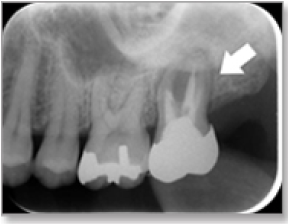

3)外傷で歯を脱臼した患者さん

18歳の女子大学生、部屋で転んで前歯を机で打ちました。来院された時には歯ぐきから出血していました。

通常のエックス線検査では正面から撮影しますので、特に歯の異常はわかりません。

しかし、CTによる検査では歯の位置を 横から診査できます。その結果、歯を打撲したことによる側方脱臼と診断されました。

歯を元の位置に整復固定を行いました。現在は神経も保存され経過良好です。CT検査でしか判別できない症状でした。

正面から撮影しますので、根の先の黒い影(矢印)以外の異常はわかりません。

歯の位置を横から診査できます。矢印の方向に歯が回転して脱臼しています。

歯を元の位置に戻して整復しました。神経も保存され経過良好です。